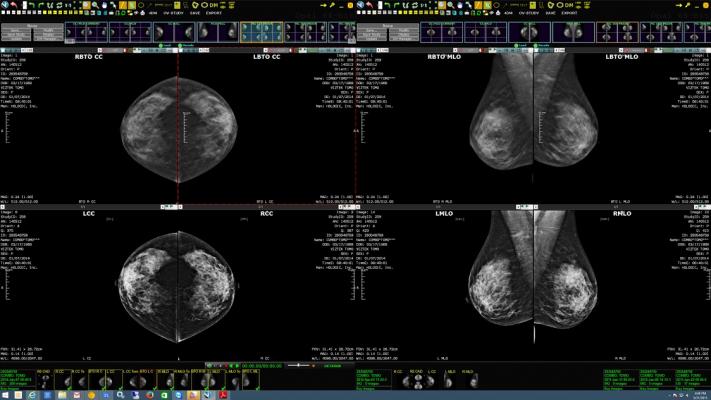

ShowCase Basic provides a full featured display of DICOM images and clips in a variety of layouts from thumbnail to 1-up and ultrasound stress echo layouts. ShowCase Premier Viewer ShowCase Premier provides you with full featured display of DICOM images and clips including 1-up 4-up 9-up 16-up 32-up and ultrasound stress echo layouts. It is very useful when a team of professionals needs to share DICOM images between them.

Imaios Dicom Viewer is an online and free DICOM viewer optimized for all web browsers on Mac and PC. The ShowCase Premier viewer combines all of the viewing features of ShowCase Basic with the ability to make on-screen measurements and burn studies to CDDVD with an optional ShowCase Onboard viewer. Our DICOM Viewer has been developed from the very beginning to focus on core functions such as measurements 3D visualisation and manipulation.

Showing all CT and MRI filtering capabilites. Each file opens up in a separate window. ShowCase Basic provides a full featured display of DICOM images and clips in a variety of layouts from thumbnail to 1-up and ultrasound stress echo layouts.